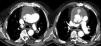

Thoracic computed tomography angiography (Figures 2 and 3) showed the Dacron tube from 2.1 cm above the aortic valve leaflets to 1.8 cm after the emergence of the brachiocephalic trunk surrounded by an image suggestive of an ascending aortic aneurysm (10 cm × 10 cm) with two active contrast leaks at the ends of the graft (type 1 endoleak), compressing the right ventricle, pulmonary artery trunk and right coronary artery.